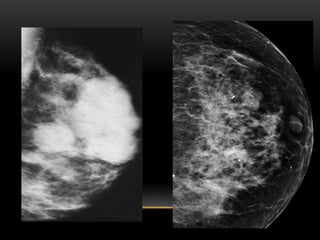

PATRÓN DEL TEJIDO GLANDULAR

MAMOGRÁFICO (COMPOSICIÓN

TISULAR MAMARIA):

1. Fibroadiposo escasa cantidad(- 25 %

glándula)

2. Fibroglandular moderada cantidad (25-50%

3. Densidad heterogénea (51-75% glándula)

4. Extremadamente denso(+ 75% glándula)

FIBROGLANDULAR ESCASA CANTIDAD

FIBROGLANDULAR MODERADA CANTIDAD

HETEROGENEAMENTE DENSO

EXTREMADAMENTE DENSO

PATRÓN DEL TEJIDOGLANDULAR MAMOGRÁFICO (COMPOSICIÓN TISULAR MAMARIA): 1. Fibroadiposo escasa cantidad(- 25 % glándula) 2. Fibroglandular moderada cantidad (25-50% glándula) 3. Densidad heterogénea (51-75% glándula) 4. Extremadamente denso(+ 75% glándula)